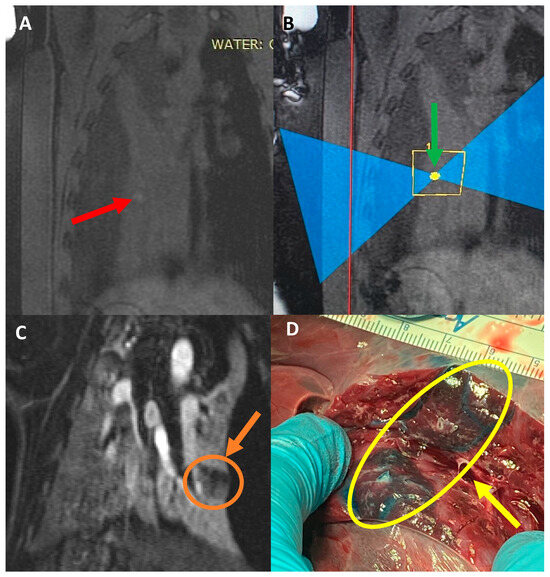

Pigs #10–11 received a liquid mixture of Vitamin E, Evans blue, and food dye in the collapsed lung parenchyma. As planned, the Vitamin E provided a hyper-intense target in the pre-treatment lung MR images (Figure 5A), and each pig received three ablations at 350 Watts for 20 s, each targeting this specific spot (Figure 5B). The ablations were visible on the post-treatment MRI with and without gadolinium contrast, but the absence of perfusion in the ablated areas was noted in the post-gadolinium MR images (Figure 5C), showing the damage of the FUS on the targeted area of the collapsed lung. Upon necropsy, there was no collateral damage noted on the skin, subcutaneous tissue, or muscle. The target sites were highly visible as a blue stain, with an area of ablation in the center, which appeared as a firm, coned area (Figure 5D).

Figure 5. (A) Coronal image of pig #11 pre-treatment. Red arrow points toward the location that the Vitamin E mixture was injected into, which shows a hyperintense region. (B) Sagittal image during treatment. Green arrow points toward the targeted location. (C) Coronal T1 weighted MR image, post-contrast showing the hypo-perfused ablated area. Orange arrow depicts the size of the ablation. (D) Necropsy of the targeted area. Yellow arrow depicts the target area generated with the dye mixture. The ablated tissue was firm and directly in the targeted area.